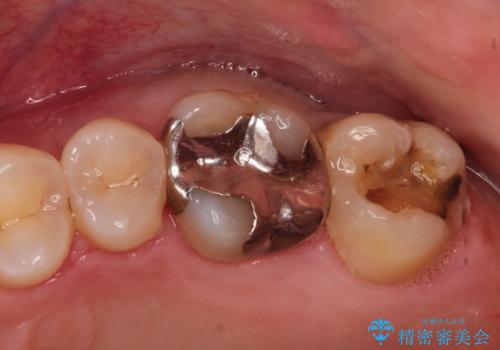

銀の詰め物が外れた。プラチナゴールドインレー

- 銀の詰め物が外れたことを主訴に来院されました。

適合の良い修復を希望されましたので、プラチナゴールドインレーにて治療を行っております。